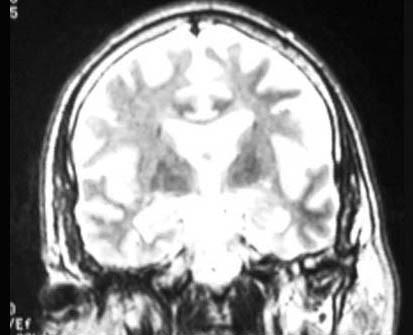

问题 某老年男性以近事记忆障碍为早期和突出表现,余无明显不适,头颅MRI表现如图,考虑诊断为 ( )

选项 A、Alzheimer病 B、CJD C、路易体痴呆 D、Pick病 E、血管性痴呆 一、单项选择题

答案 A